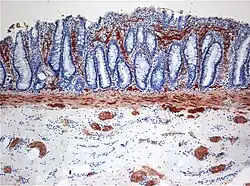

| Histopathology of Hirschsprung disease showing abnormal acetylcholine esterase (AchE)-positive nerve fibers (brown) in the mucosa | |